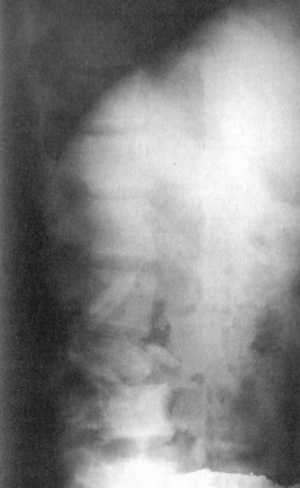

При переднебоковой декомпрессии в грудном и поясничном отделах позвоночника

осуществляется резекция поперечных отростков, одного-двух вертербральных концов

ребер с экзартикуляцией головок в грудном отделе. Затем постепенно удаляются

суставные отростки и корень дуги поврежденного позвонка. Освобождается заднебоковая

поверхность поврежденного позвонка и вышерасположенный межпозвонковый диск.

Декомпрессия начинается с диск-эктомии поврежденного диска и резекции задневерхнего

участка тела поврежденного позвонка (клин Урбана). Следующим этапом разработанного

способа является выполнение каналов с обеих сторон в телах выше- и нижерасположенных

позвонков, введение в них костных кортикальных аллотрансплантатов и фиксация

их по типу ромба. Дополнительно осуществляется задний спондилодез длинными

кортикальными ал-лотрансплантатами или металлическими пластинками Вилсона

(рис. 12.4-6).

Рис. 12.4. Скиаграмма хирургического

вмешательства при повреждении L3 позвонка |

Рис. 12.5. Рентгенограмма после хирургического

вмешательства при повреждении L3-позвонка (боковая проекция) |

Рис. 12.6. Рентгенограмма после хирургического

вмешательства при повреждении L3-позвонка (прямая проекция) |